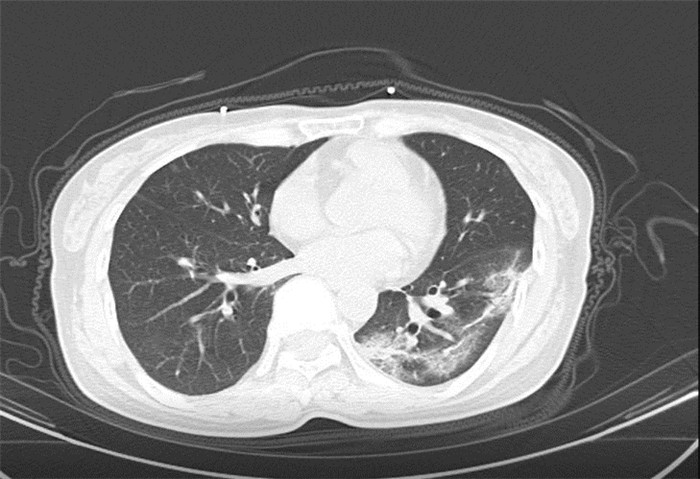

方舟CT(CT Ark)可以滿(mǎn)足全面的臨床功能,配置16層、32層、64層、128層CT,實(shí)現(xiàn)了低劑量掃描要求,配合NDI微劑量迭代技術(shù),智能毫安調(diào)控技術(shù),使各種場(chǎng)合下、各部位低劑量掃描得以實(shí)現(xiàn);超高分辨率CT病灶靶掃描,使病灶的密度顯示更加精確,能夠顯示病灶內(nèi)輕度的密度變化,有利于小病灶的密度定量分析和及時(shí)診斷。